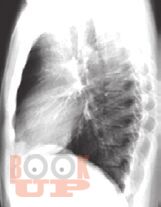

В настоящей монографии подробно описаны и проиллюстрированы изменения легких, сердца и костной системы при различных патологических состояниях в пульмонологии, кардиологии и ревматологии. Сопоставлены клиническая и рентгенологическая картины при различный нозологических формах проявления многих заболеваний. Все представленные результаты рентгенологических исследований верифицированы и подтверждены клинически. Монография предназначена для врачей-рентгенологов, пульмонологов, кардиологов и ревматологов, а так же врачей других специальностей, занимающихся диагностикой и лечением органов грудной клетки.